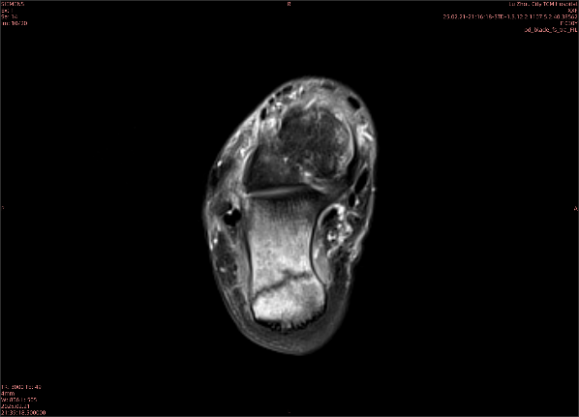

举例图像

图1

专业解释看不懂没关系,大家看图1和图2就可以了,这是同一个患者跟骨的磁共振和CT图像,图1的红色箭头指示的黑线就是磁共振图像显示的骨折线,一目了然。而对比图2的CT图像上并未显示异常。